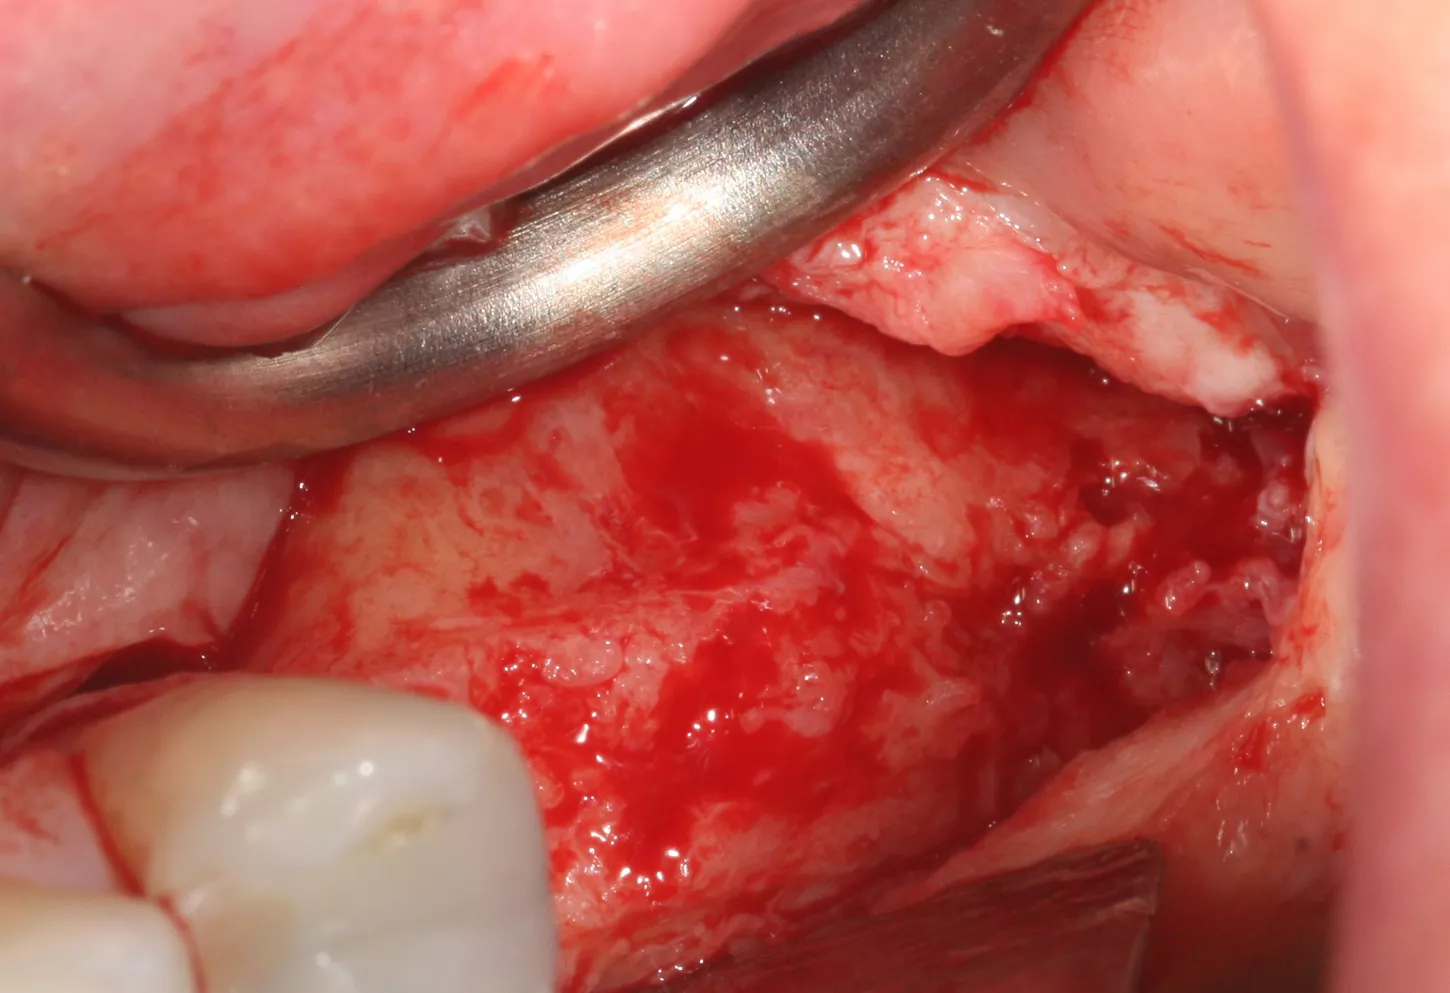

6. A lateral sinus lift was performed by creating a 7 × 5 mm window using a round tungsten carbide bur followed by a diamond bur.

7. The bony window was removed and placed in saline solution so that it could be placed back in position after grafting. The Schneiderian membrane was released without perforation.

8. The sinus was elevated with cortical/cancellous allograft of a particle size of 0.5 mm and volume of 1.5 cc.